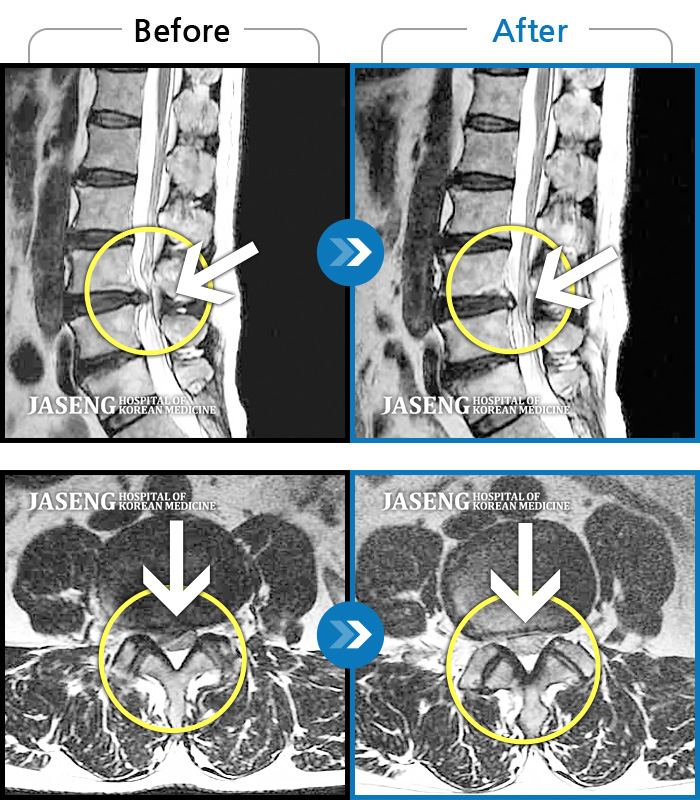

Xray 와 MRI 검사를 받았고

4번5번 척추사이 협착증과 유종이 원인이라고 하면서

한방 비수술치료로 2달동안 치료하면 나을 수가 있다고 말씀하셨고, 만약 한방치료로도 낫지 않으면 큰 대학병원 수술을 받아야 한다고 하면서 한방 비수술 치료를 권장해 주셔서, 박정우원장님의 치료를 받기 시작하였다.

12월20일까지 두 달 정도 치료를 마친 결과,

거의 정상상태로 회복 되었으며, 현재는 집에서 꾸준하게 체조와 가벼운 운동으로 관리하고 있습니다.